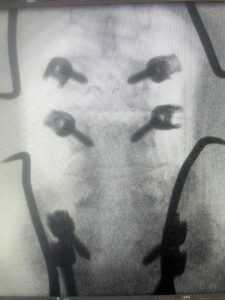

Fig: 2a: AP and lateral intraoperative fluoroscopic images demonstrating good placement of L2-3 pedicle screws